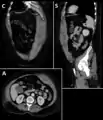

Rectus sheath hematoma seen on axial CT – with active bleeding under Marcoumar